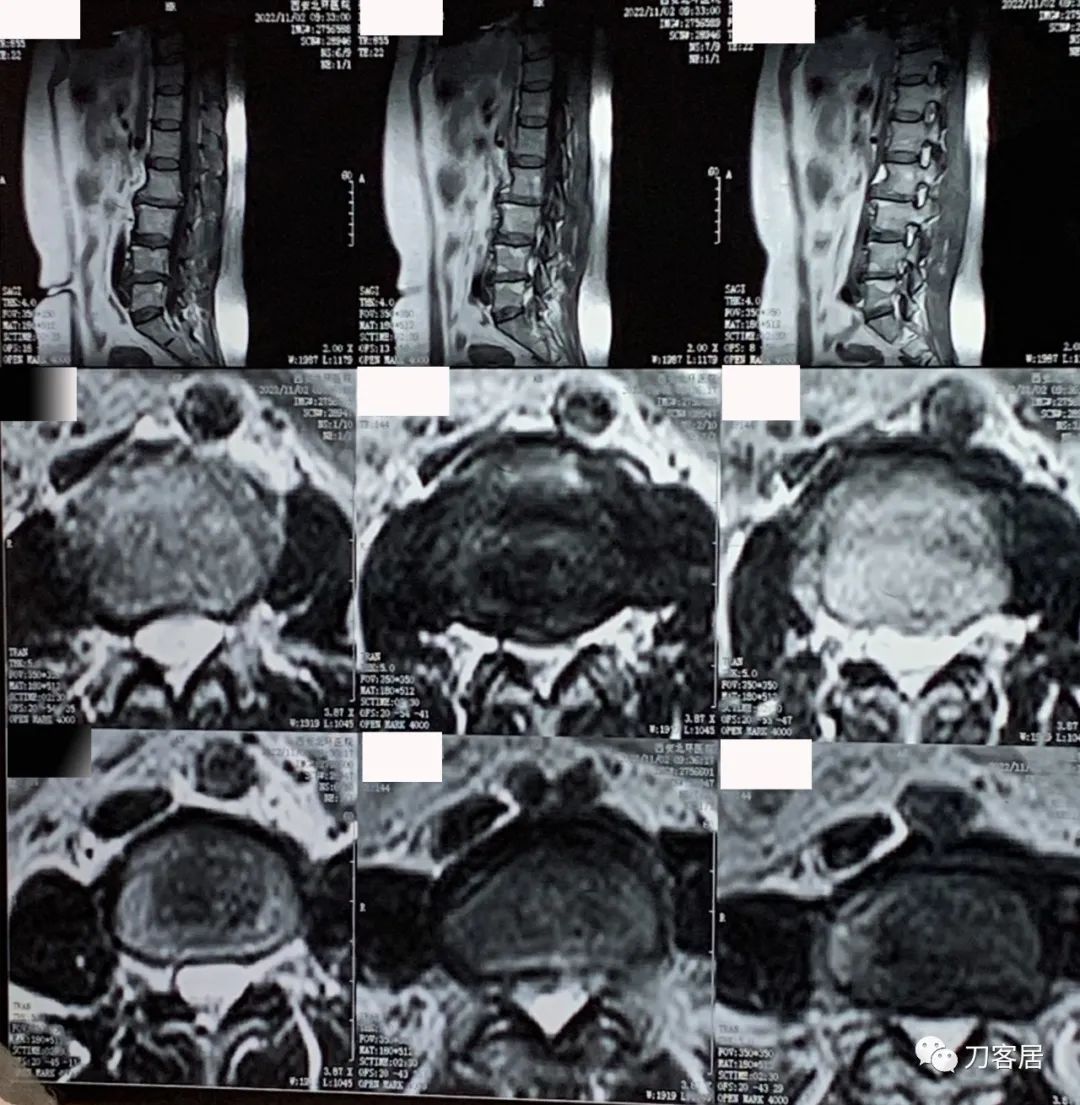

图4. 20221102西安北环医院腰椎MRI04